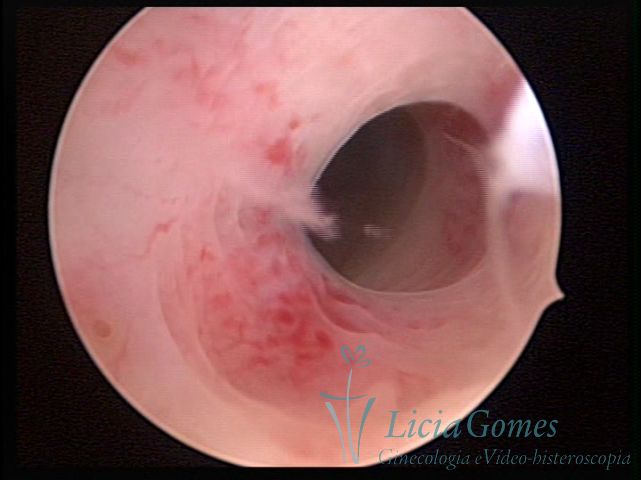

First part or proximal section or lower section:

During the proliferative phase, a light, crystalline mucus with a low adherence to the scope is found. The crypts and buds are a little swelled and vascularized, microvesicular, resembling grape clusters.